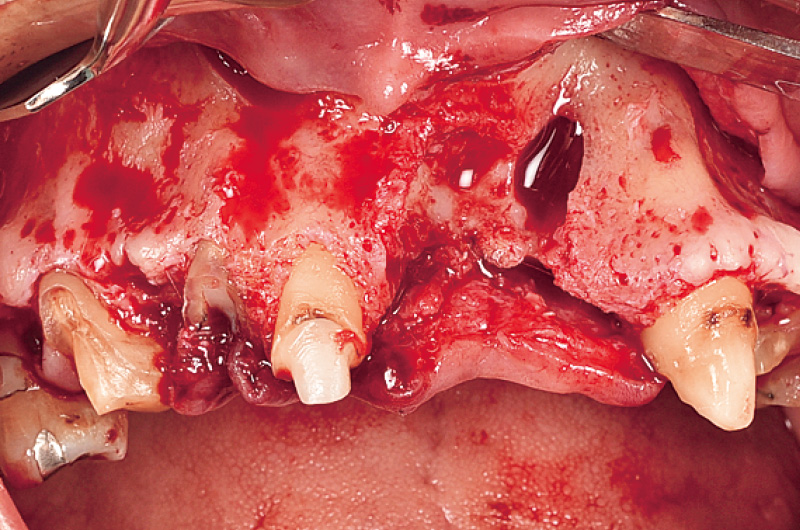

13, 23の遠心隅角に縦切開を行い、₁₂欠損部に対しては、唇側寄りの歯槽頂切開を行った。フラップを剥離・翻転後、骨に付着している軟組織を除去し骨欠損形態を明示した。欠損部顎堤は、鼻腔底に近い部分までの骨の喪失を認め、頰舌的に1層の薄い骨が確認でき、また口蓋側の骨壁も喪失している(図4, 5)。下顎右側頰棚よりボーンスクレーパーにて自家骨を採取し、骨移植材として填入した。

図4 21, 22相当部は、根尖付近まで骨の喪失を認める。 -

図5 欠損部顎堤は、著しい骨の喪失が確認できる。 -